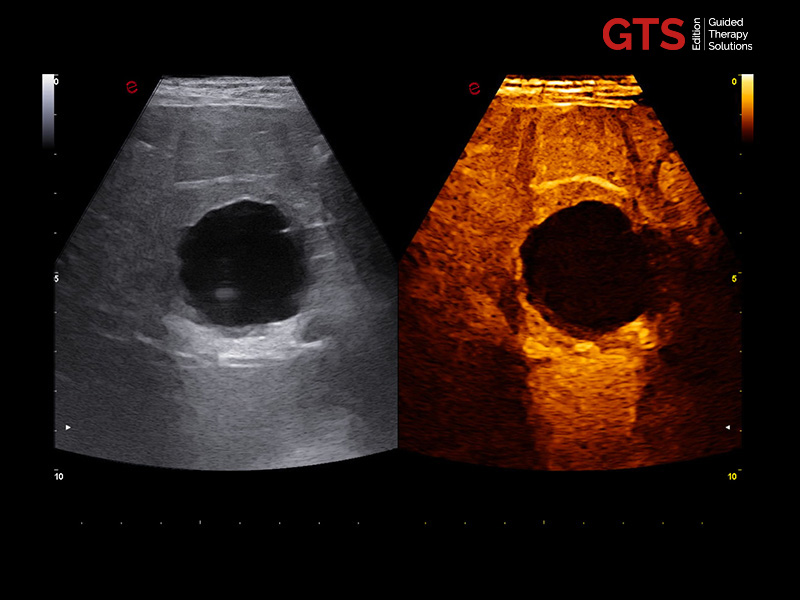

CnTI™ is Esaote’s CEUS technology that helps to identify suspicious areas in the prostate, helping to target areas to be biopsied. Furthermore, it can be used for focal therapy follow-up.

The CnTI™ guarantees a very high sensitivity in detecting contrast media agents, while maintaining long persistence of the contrast bubbles.

CnTi™ (Prostate perfusion study - Suspected anterior lesion)